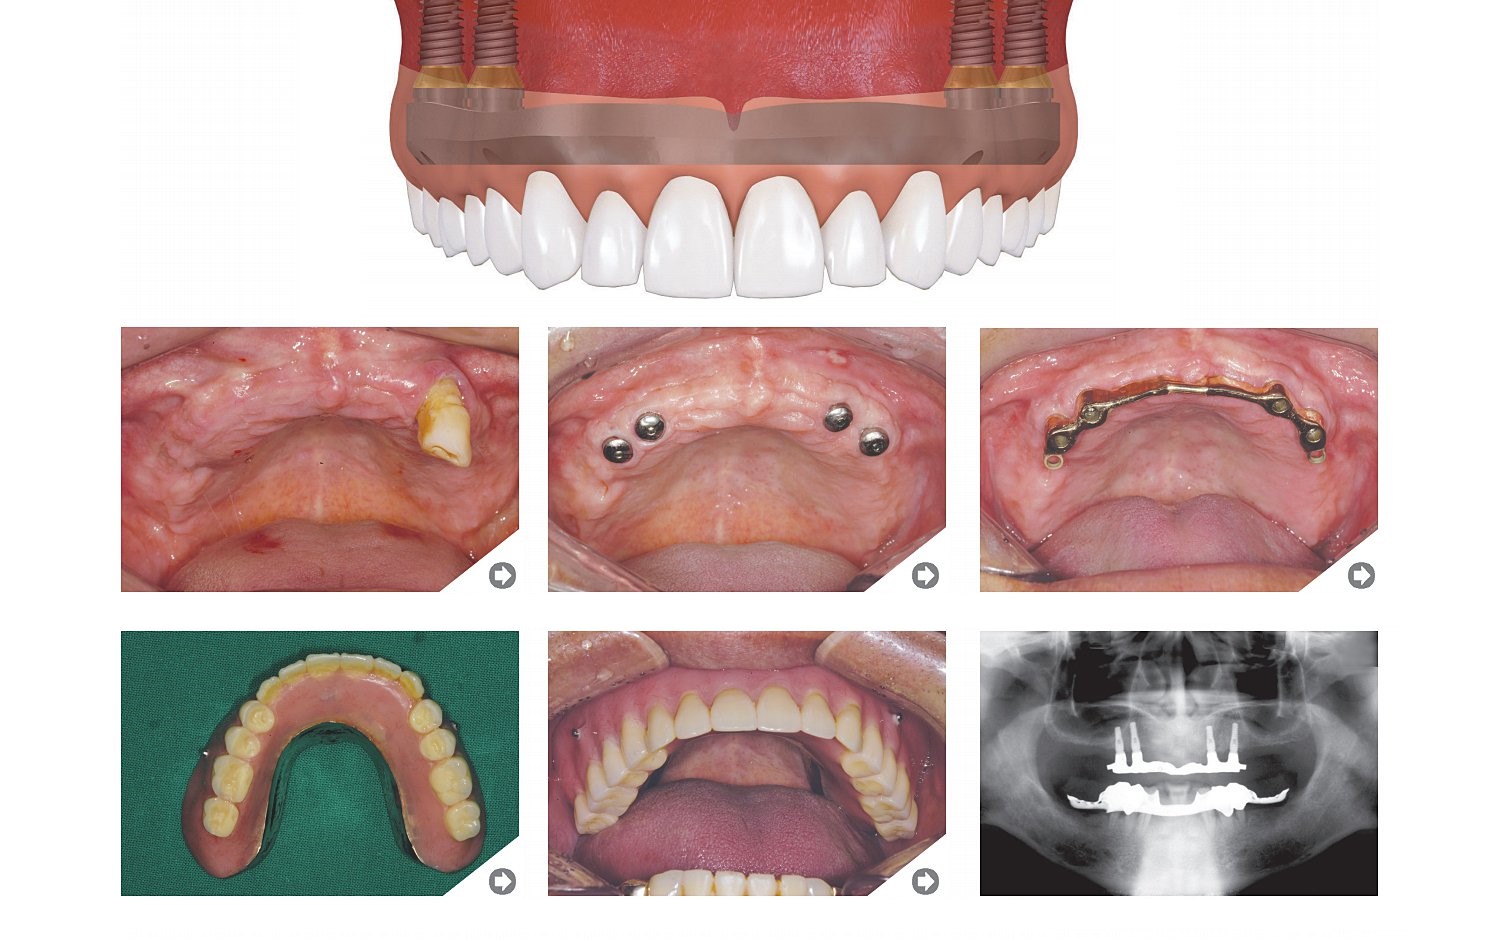

Trūkst visu zobu

Neizņemama protēze

Implanti izņemamām protēzēm